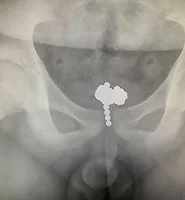

| 70개의 자석구슬을 몸속에 넣은 11살 중국소년 (0) | 2019.04.11 |